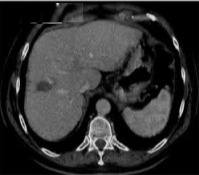

69 岁的男性患者,患有丙型肝炎相关肝硬化,其肝脏增强扫描(S8)中可见一个 22 mm 肝细胞癌结节。